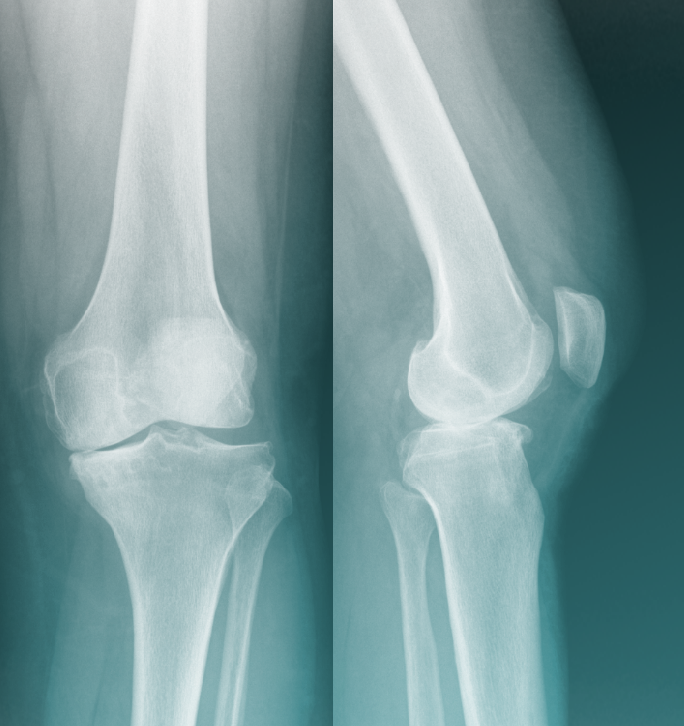

L’arthrose est une usure du cartilage, la surface de glissement de l’articulation1. Cette usure est irréversible et entraîne un contact direct « os contre os », rendant le mouvement difficile et douloureux.

Arthrose du Genou

Dans votre cas, l’arthrose n’est pas seulement due à l’âge, mais souvent à un défaut d’axe de la jambe appelé Genu Varum (jambes arquées).

• Le mécanisme : À cause de cette courbure, tout le poids de votre corps passe par la partie interne du genou.

• La conséquence : Cette surcharge mécanique écrase le ménisque et le cartilage de ce côté, provoquant une usure prématurée alors que le reste du genou est sain.